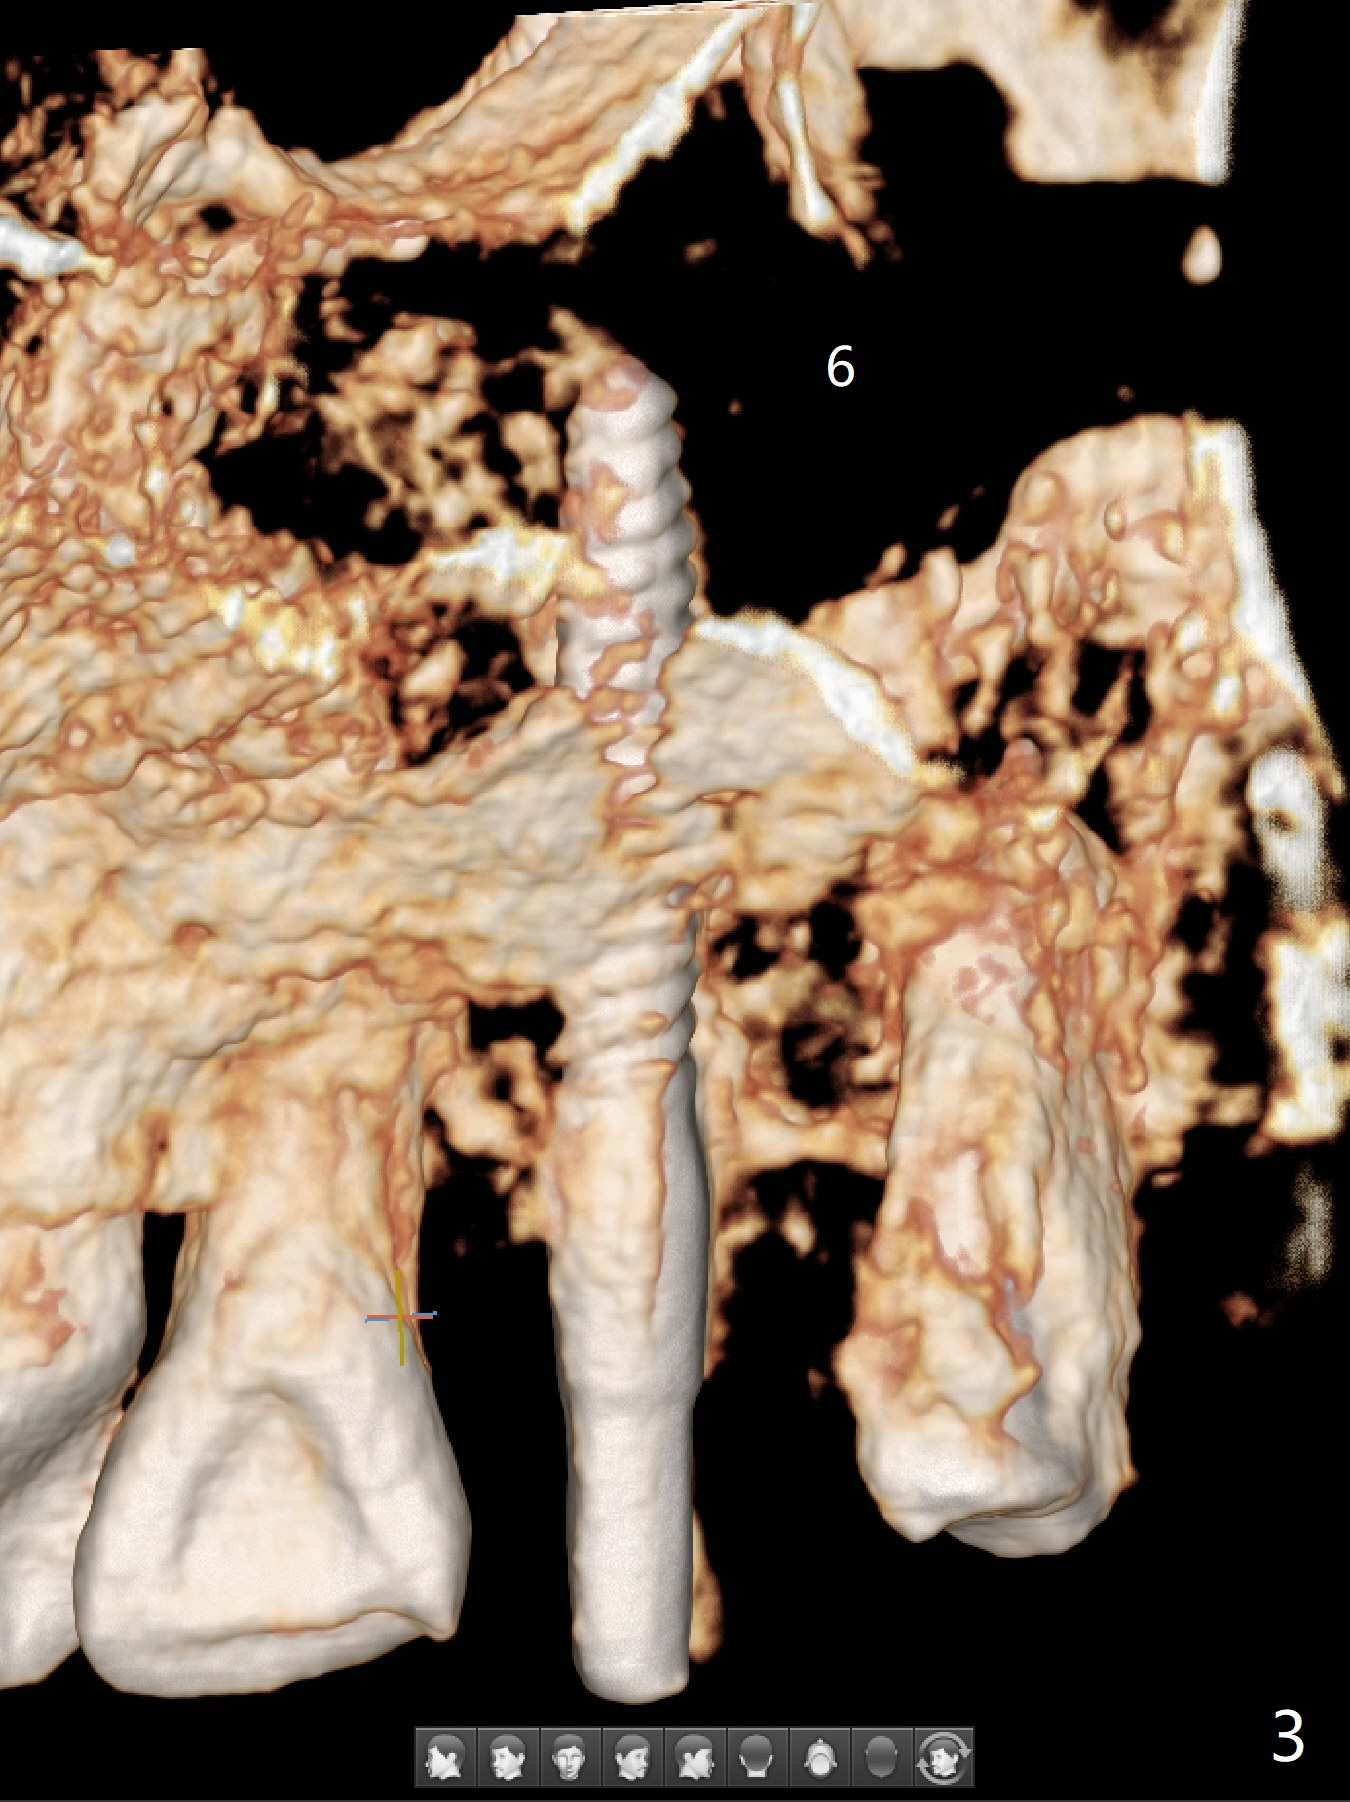

Osteotomy starts with guide and 2.2 mm drill for initial 3.5 mm palatal. A semilunar incision is made buccal to remove the impacted canine (#6 by sectioning). With direct vision buccal and palatal, the final osteotomy is finished free hand with 1.2 and 1.5 mm drills. Initially buccal perforation occurs, the osteotomy route is corrected later (Fig.1). When a 2.5x15 mm 1-piece implant is being placed, it perforates into the buccal concavity again. After redirection, the trajectory seems to be acceptable (Fig.2: CT coronal section). Three coronal implant threads are exposed partially palatal (Fig.3: CT 3-D palatal view). The implant is then turned 2-3 times with insertion torque reaching 40 Ncm. The incision is closed with suture following Osteogen plug placed in the most coronal portion of the socket (Fig.4 P) and allograft (*) in the remaining socket around the apical portion of the implant as well as palatal. The incision does not heal 1 month postop (Fig.5). PRF membrane will be placed next visit. Next visit the wound in fact is healing (Fig.6). PRF is unnecessary. The patient will return for impression 3 months postop. To be cosmetically pleasing, prepare local anesthetic and Laser for gingivectomy (Fig.7 red curved line). There is no bone loss around the implant 3.5 months postop (Fig.8). With topical, minor gingivectomy with laser creates papillae mesial and distal to the implant (Fig.9, 10 (incisal view)). After reline, there is appearance of a canine (Fig.11). The patient returns for impression 5 months postop; there is bone around the apex of the implant (Fig.12 *). The hard and soft tissues remain healthy when final restoration is delivered (Fig.13,14). The buccal plate reforms and #6 socket heals 12 months postop (6 months post cementation, Fig.15). The gingiva remains healthy at #4-6 nearly 2 years post cementation (Fig.16).